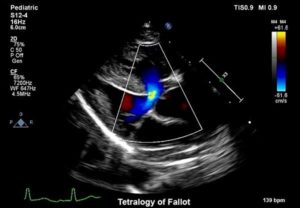

Ein Herzfehler, noch dazu bei dem winzigen Herzen eines Neugeborenen, lässt sich mit herkömmlichen zweidimensionalen Ultraschallbildern nicht gut erkennen. Die Kinderherzspezialisten nutzen daher moderne Hochleistungs-Ultraschallgeräte: Die 3D-Echokardiographie stellt das kleine Herz dreidimen-sional in Echtzeit dar. Auf dem Monitor erscheint es räumlich und wirklichkeitsnah.

Größe und Funktion der Herzkammern können frühzeitig analysiert werden, um die Weichen für eine erfolgreiche Therapie zu stellen. Bei Untersuchungen bleiben den kleinen Patienten dank der detaillierten 3D-Ultraschallbilder schmerzhafte Eingriffe, Katheter, Narkose und Röntgenstrahlen erspart. Kommt es zur Operation, kann der Kinderherzchirurg das Operationsfeld bereits im Vorfeld am Computer simulieren.

Die Abteilung für Kinderkardiologie am Universitätsklinikum Bonn arbeitet bereits mit der 3D-Echokardiographie. 2016 wurde eine neue Software gekauft. Für das neue Eltern-Kind-Zentrum – kurz ELKI – im Universitätsklinikum auf dem Bonner Venusberg möchten die kinderherzen ein 3D-Ergänzungsmodul anschaffen. Es verbessert die Untersuchung der Herzkinder, denn es ermöglicht eine rasche und zuverlässige Auswertung von 3D-Echokardiographien.

Die Software wurde bereits ausführlich getestet. Sie ermöglicht neben der Auswertung von 3D-Echokardiographien des rechten und linken Herzens auch eine einzigartige Bestimmung der Herzmuskelfunktion. Dies ist besonders wichtig bei Einkammer-Herzen sowie bei Kindern mit Herzmuskelerkrankungen. Für die Installation dieser neuen Software wird außerdem eine Workstation mit erhöhter Performance benötigt.